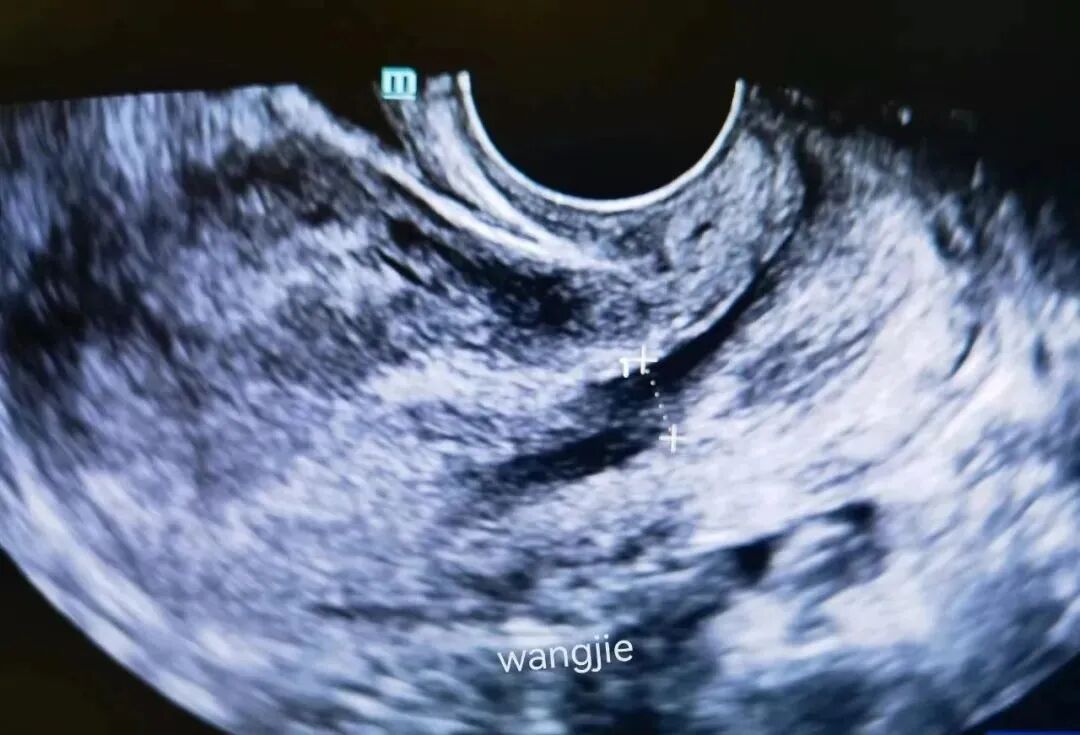

🔹超声检查

蜕膜息肉超声表现为子宫颈管内低至中等回声团块,特征为子宫颈内口扩张,团块贯穿子宫颈管,与宫腔下段蜕膜组织界限不清。息肉可随体位及宫腔压力变化活动。